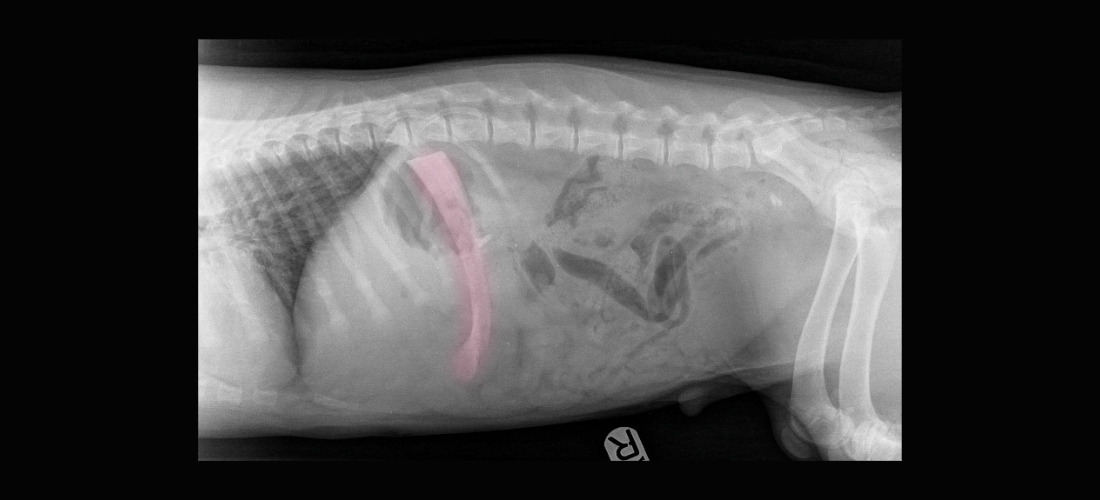

Holly said: “They took him away for X-rays, and to my horror, they found a rib bone from the previous night’s Chinese takeaway stuck in his stomach. The vets and vet nurses needed to operate immediately to remove it.”

Senior Veterinary Surgeon, Susan Hermit, said: “We were absolutely amazed to see the size of the rib bone in Rex’s stomach - we couldn’t believe he’d managed to swallow it whole! There was a high risk that the sharp edges of the bone could puncture his stomach with life-threatening consequences, so we took him to surgery right away. Luckily we were able to remove the bone before any serious damage was done.”